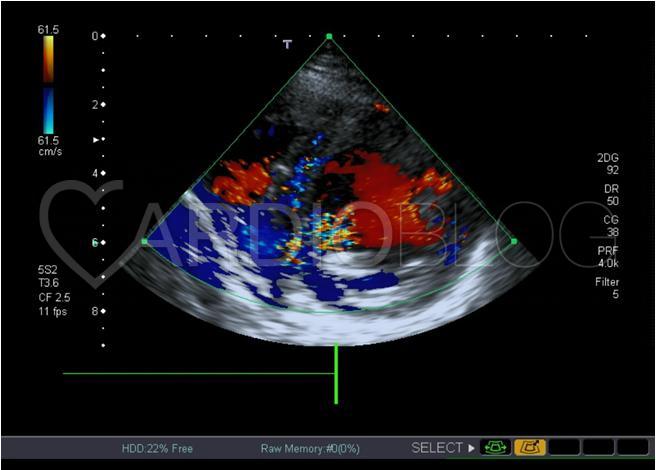

Az echocardiographias vizsgálat jó bal kamra funkciót írt le, enyhe fokú mitrális és tricuspidális regurgitációval, regionális falmozgászavar nélkül, azonban a septumban dilatált perforáns ágaknak megfelelő kép, fokozott septalis áramlás ábrázolódott.